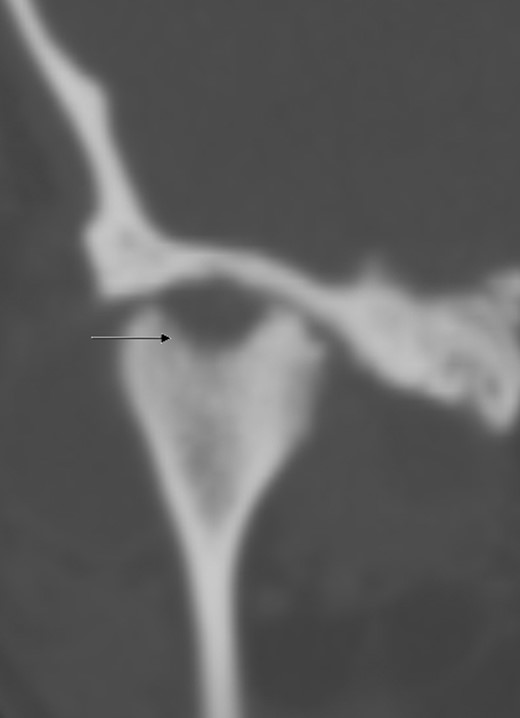

Approximately 4 months later symptoms returned. A computed tomography (CT) scan of the head was ordered by the oncologist. An osteolytic lesion and partial sclerosis of the right condylar head and neck were found, as well as effusion in the right TMJ (Fig. 1). The signs were interpreted as arthritis of the TMJ.

CT scan of the head (coronal section), arrow indicates osteolysis of the right condylar head.